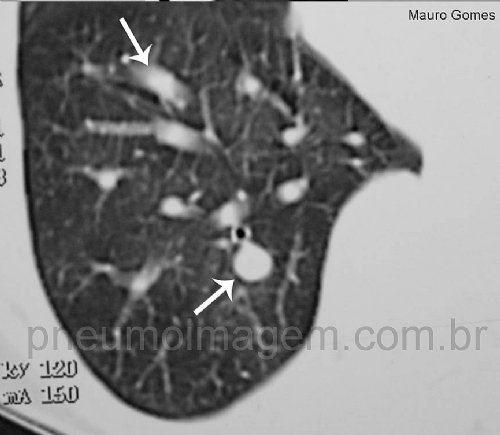

A hipertensão pulmonar tromboembólica crônica (HPTEC) é uma complicação rara da embolia pulmonar aguda, seja sintomática ou não. A oclusão das artérias pulmonares proximais por material fibrótico intravascular, em combinação com uma microvasculopatia secundária de pequenos vasos, leva ao aumento da resistência vascular pulmonar e à insuficiência cardíaca direita progressiva. O mecanismo responsável pela transformação dos coágulos vermelhos em restos de material fibrótico ainda não foi elucidado.

Em pacientes com HPTEC, o diagnóstico é suspeitado quando uma cintilografia pulmonar de ventilação / perfusão mostra defeitos de perfusão incompatíveis e é confirmado por cateterismo cardíaco direito e por imagem vascular. Hoje, além da anticoagulação vitalícia, as modalidades de tratamento incluem a cirurgia.